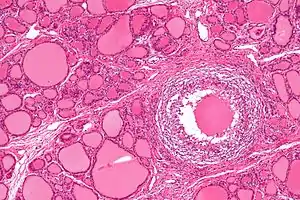

| Micrograph showing a granuloma in subacute thyroiditis. H&E stain. | |